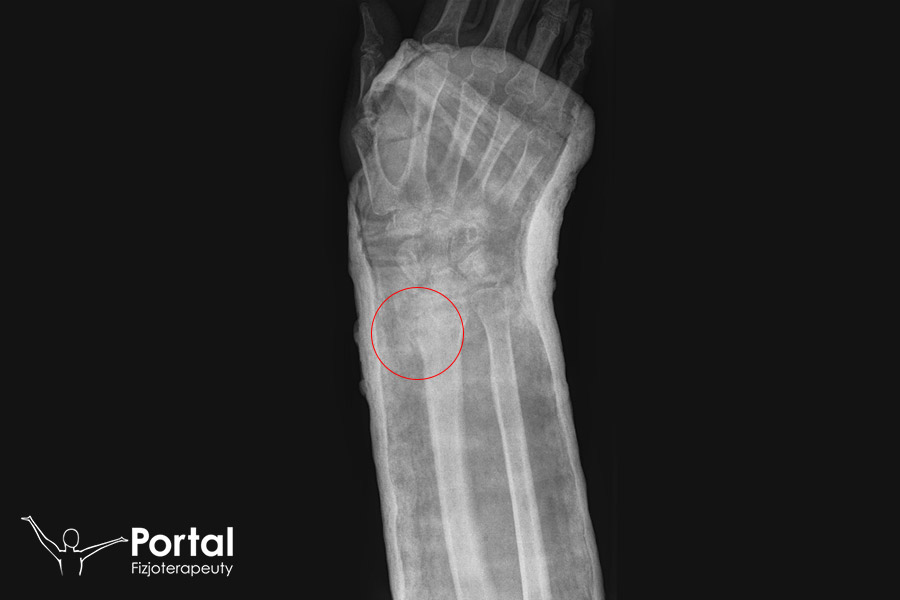

Złamanie Collesa stanowi najczęstszy typ złamania nasady dalszej kości promieniowej. Charakteryzuje się odchyleniem dalszego fragmentu tej kości do góry lub